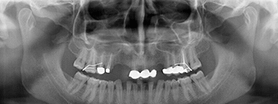

Pro Patient: Our state-of-the-art cone-beam computed tomography (CBCT) technology could selectively image the sinus, oral maxillofacial, para-nasal sinuses, ear & throat regions.

Proactive Dental Management thru our 3D Imaging Manipulation Software

With Oral Maxillofacial CT Scans, your dentist enhances his ability to proactively manage your health concern thru accurate diagnosis & better treatment planning. Moreover, the patient benefits from a painless,low radiation dose CT Scan procedure.